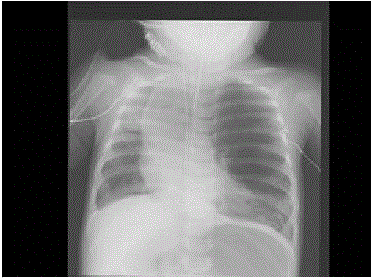

问题 女婴,6个月,呼吸窘迫,左肺呼吸音弱、偶可闻及哮鸣音,请结合影像图像选择,最可能的诊断( )

选项 A、先天性囊性腺瘤样畸形 B、支气管囊肿 C、细支气管肺炎 D、胸腔积液 E、先天性肺气肿

答案 E